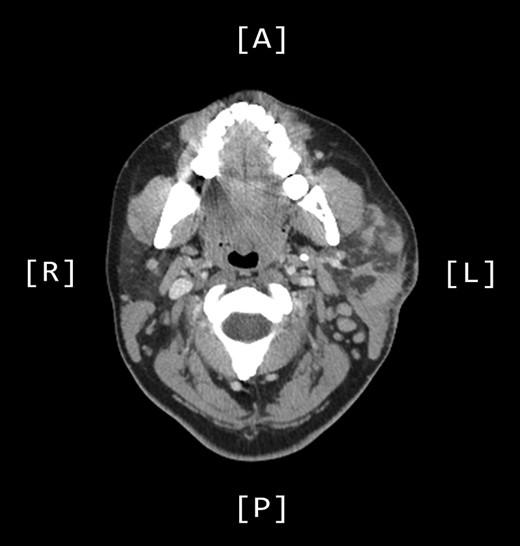

A computed tomography (CT) scan demonstrated left parotid multifocal soft tissue abnormality and enlarged left-sided cervical lymph nodes, with prominent superficial left supraclavicular fossa lymph nodes (Figs 3 and 4).

Axial CT sinuses (with contrast) showing left parotid multifocal soft tissue abnormality and enlarged left-sided cervical lymph nodes.